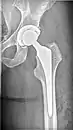

Hip replacement

When patients have later stages of ONFH most other treatment options are not successful or even worth trying. Thus the only option is total hip replacement where the FH and the pelvic portion of the joint are both replaced or one part of the hip joint is replaced. Many surgeons do choose to just replace the hip altogether in some mild cases because hip replacements have a longer success rate and most of the time if you try to do partial replacements or FH sparing techniques that are not totally successful later in life a hip replacement is needed. A lot is needed to take into consideration including age and progression.[3]